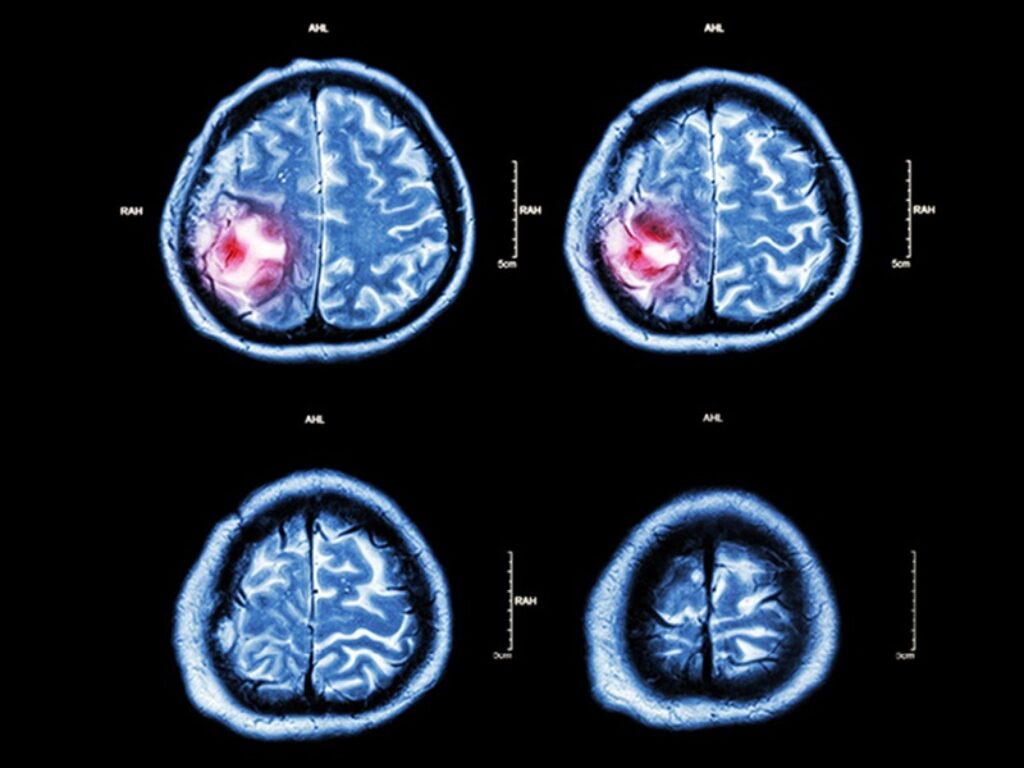

Il trattamento con andexanet in persone con emorragia intracerebrale acuta in terapia con inibitori del fattore Xa ha portato a una minore espansione del volume dell’ematoma

Il trattamento con andexanet, agente di inversione del sanguinamento, in persone con emorragia intracerebrale acuta in terapia con inibitori del fattore Xa ha portato a una minore espansione del volume dell’ematoma, ma è stato associato a eventi trombotici. Lo ha dimostrato lo studio ANNEXA-I, i cui risultati sono stati pubblicati sul “New England Journal of Medicine”.

L’emorragia cerebrale acuta è associata a un’elevata morbilità e mortalità e l’espansione dell’ematoma è una complicanza che può verificarsi nei pazienti che assumono anticoagulanti orali, compresi gli inibitori del fattore Xa come apixaban e rivaroxaban.